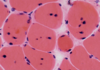

Segmental necrosis

Segmental necrosis

Segmental necrosis

Muscle necrosis and regeneration

Muscle regeneration - myotubule grows + differentiates + develops sarcomeres (striation) and nuclei move to the periphery (requires intact basal lamina)